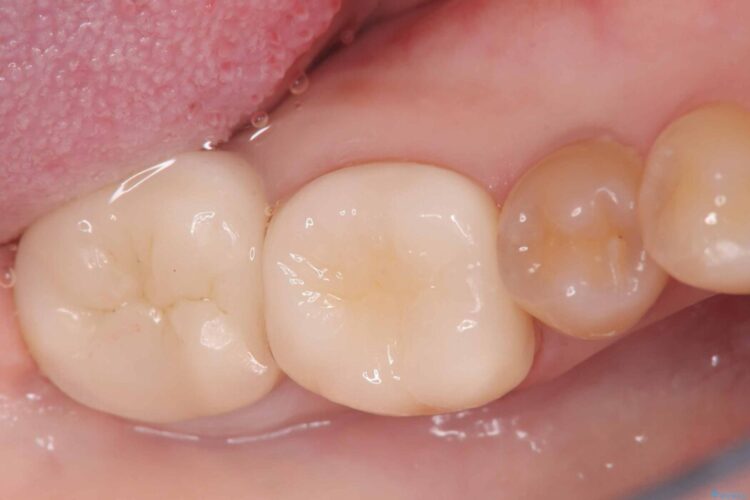

部分的断髄法(VPT)とセラミック修復

部分的断髄法(VPT)とセラミック修復 ビフォー 部分的断髄法(VPT)とセラミック修復 アフター

「冷たいものが強くしみる」とご相談にいらした患者様です。